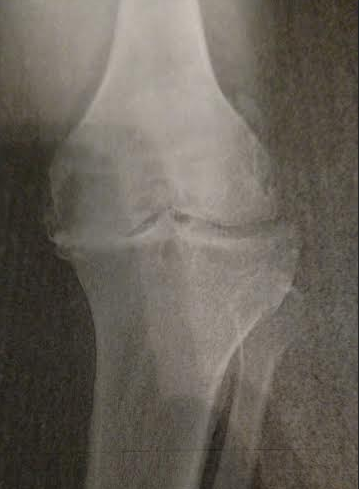

A Regular Knee!

My old right Knee (x-ray), Bone on Bone!